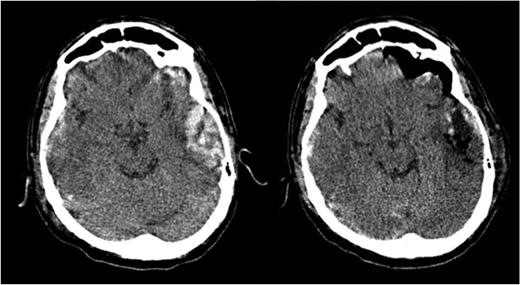

Brain computed tomography (CT) scan showed a temporal hematoma with 30 ml of volume, extending from the temporal posterior region to the anterior compartment of the right media fossa. The volume and the location of the hematoma implicate in a high risk of brain stein compression.

The patient was discharged from hospital after 48 h of surgery. The comparison between the pre- and postoperative CT scans is shown in Fig. 2.